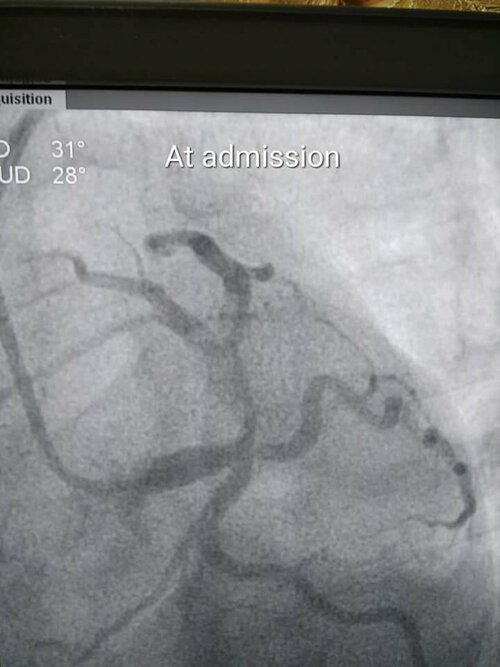

40 yr male diabetic patient ,came with Acute Anterior wall Myocardial Infarction ( Heart attack) with cardiogenic shock ( low blood pressure) at 7: 30...